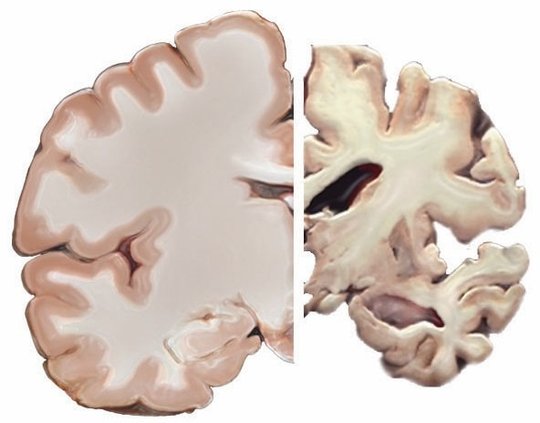

This photo illustration from the National Institute on Aging compares the cross-section of a healthy brain, left, with one affected by severe Alzheimer’s disease (Photo courtesy of the National Institute on Aging, National Institutes of Health).